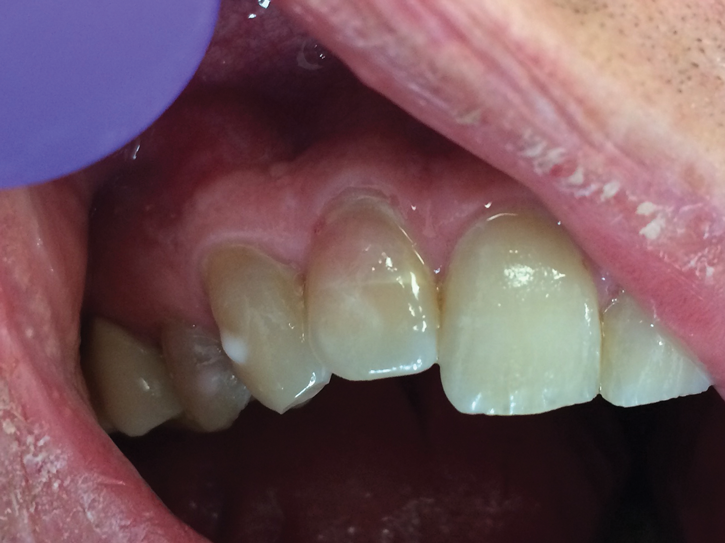

Early-stage ECR lesions may not be readily detected on clinical examination. Because the portal of entry normally occurs cervically, ECR lesions are often only palpable subgingivally. Cervical cavitation may be present and can be diagnosed by probing with an explorer-type instrument. When an explorer is used, ECR lesions will feel hard and scratchy like dentin with an irregular surface not like caries lesions, which feel sticky or soft.7,17 The appearance of knife-edge borders around such a cavitation can also help to differentiate ECR from root caries.18 Furthermore, a pink spot or banding may be present at the cervical aspect of the tooth overlying the resorption cavity; however, this finding occurs rarely and may also infrequently be associated with internal root resorption lesions (Figure 5 and Figure 6).19 The pink discoloration results because the granulation tissue of the resorptive defect has become visible through the overlying dental hard tissues. Generally, the gingiva adjacent to ECR lesions can be inflamed and may exhibit easy bleeding on probing due to its vascularity.1,7,14,19 Therefore, the presence of irregular, inflamed, and/or hyperemic gingiva may serve as early indicators of an ECR lesion. More advanced lesions may entrap debris within them, creating a secondary periodontal abscess or caries lesion with associated signs and symptoms.14,6